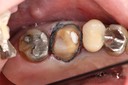

Wayne Chin #14 pre-op